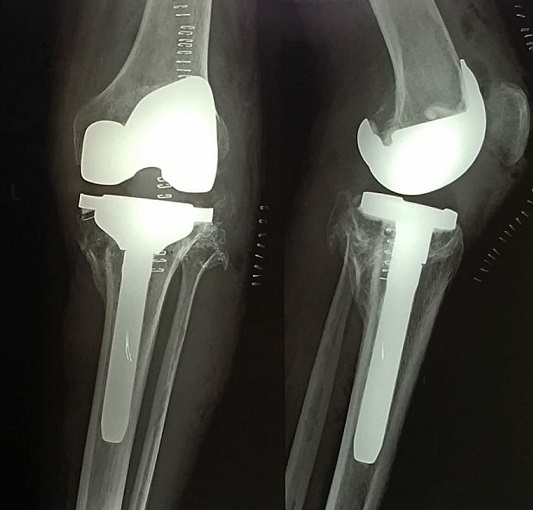

Stryker Triathlon Technique Guide. Triathlon® Cementless Fixation you can trust. Stryker Stryker Orthopaedics wishes to thank the global Triathlon Tritanium Knee System 3 Triathlon was designed to incorporate some of the most studied features of Stryker's prior designs that have been shown to address many of the main reasons for revision TKA, such as instability, patellofemoral tracking.

Total Knee Replacement Using Stryker Triathlon System, 45 OFF. Varus/Valgus Adjustment > Varus/Valgus Alignment can be changed by 3 Triathlon was designed to incorporate some of the most studied features of Stryker's prior designs that have been shown to address many of the main reasons for revision TKA, such as instability, patellofemoral tracking.